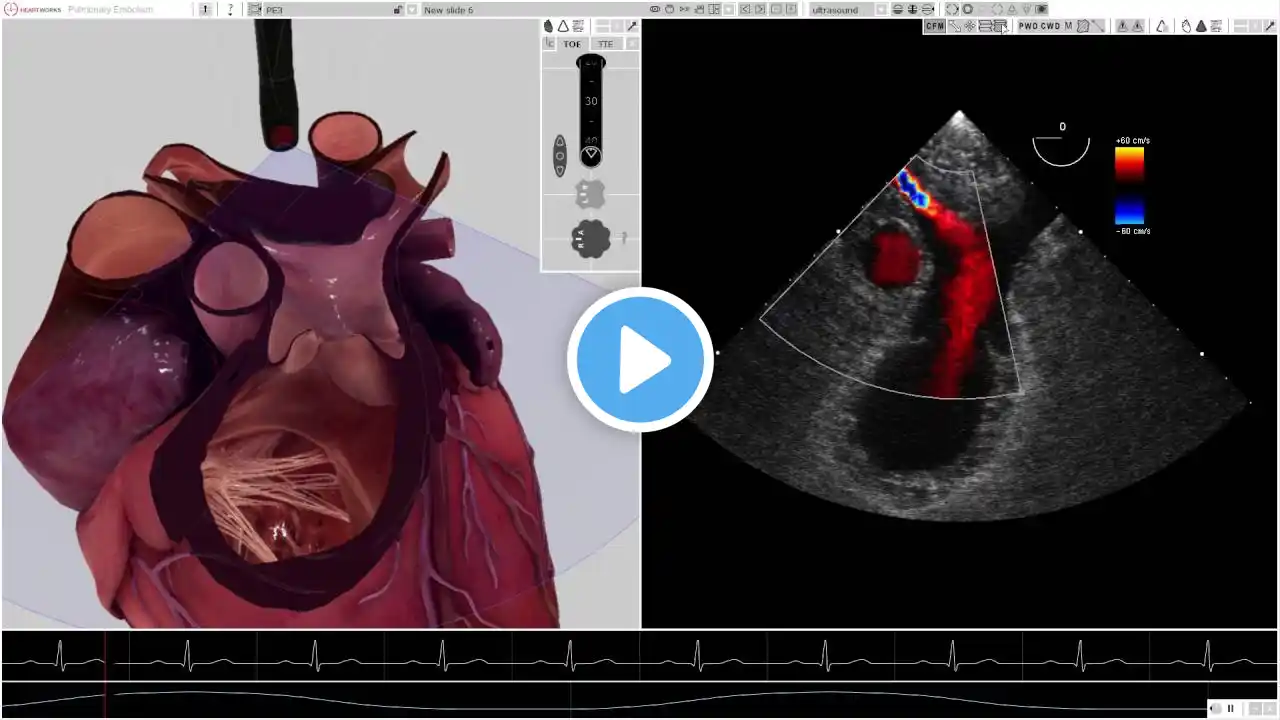

POCUS Cases 2: Pulmonary Embolism

POCUS Cases is an original EM Cases video series led by Dr. Robert Simard, an Emergency Physician at North York General Hospital and Sunnybrook Health Sciences Centre in Toronto. He completed a POCUS fellowship at NOSM and teaches POCUS nationally and internationally. Visit https://emergencymedicinecases.com/ for up to date content.